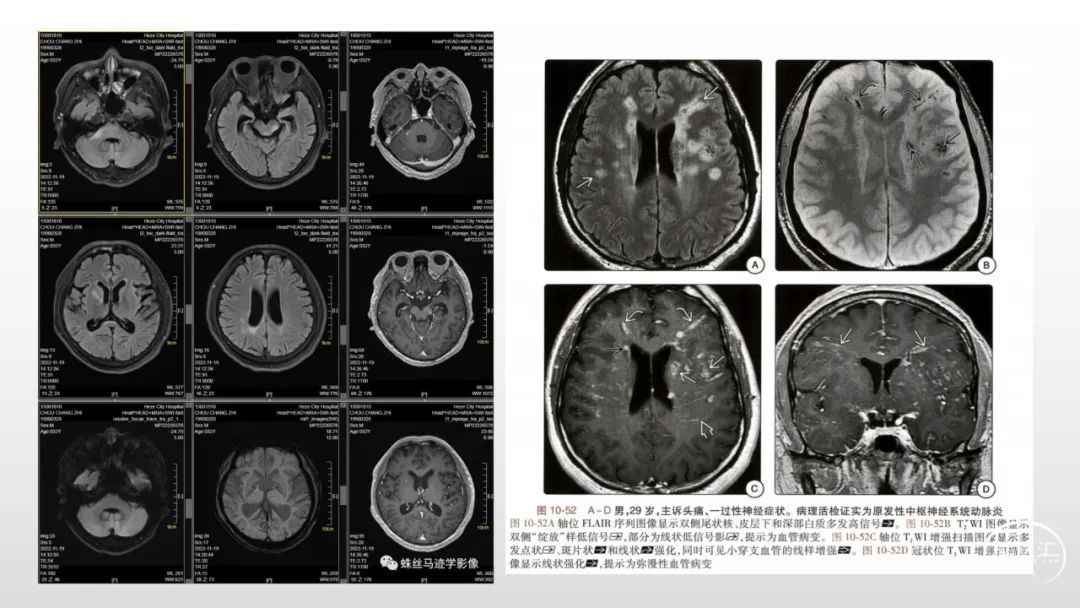

颅脑影像诊断基础知识讲座:感染和免疫性疾病2

马洪舟

菏泽市立医院